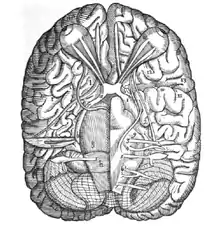

Illustration from De Nervis Opticis by Varolius | |

He is best remembered for his work on the cranial nerves. He was the first to examine the brain from its base upwards, in contrast with previous dissections which had been performed from the top downwards. In 1573 he published this new method of dissecting the brain whereby he separated the brain from the skull and began the dissection from the base. Varolio described many of the brain's structures for the first time including the pons or pons Varolii which is a reflex center of respiration and a communication bridge between spinal cord and brain, the crura cerebri and the ileocecal valve.[3]

De Nervis Opticis nonnullisque aliis praeter communem opinionem in Humano capite observatis. Ad Hieronymum Mercurialem, Patavii apud Paul et Anton. Meiettos fratres, 1573, 8º, 8 and 32 leaves. It consists of a letter to Girolamo Mercuriale, dated 1 April 1572, his answer, and Varolius' reply to the latter. Appended are three woodcuts pertaining to the brain and drawn by Varolius himself. The engraving is somewhat crude, yet distinct and instructive.[6]

A second work by Varolius, a teleologic physiology of man, was published for the first time after his death: Anatomiae sive de resolutione corporis humani ad Caesarem Mediovillanum libri iv, Eiusdem Varolii et Hieron. Mercrialis De nervis Opticis, etc. epistolae, Francofurti, apud Joh. Wechelum et Petr. Fischerum consortes, 1591, 8º, 8 and 184 pp. This contains one illustration. The former book is republished as a part of this work with unchanged text and the woodcuts recarved in a somewhat different manner.[6]